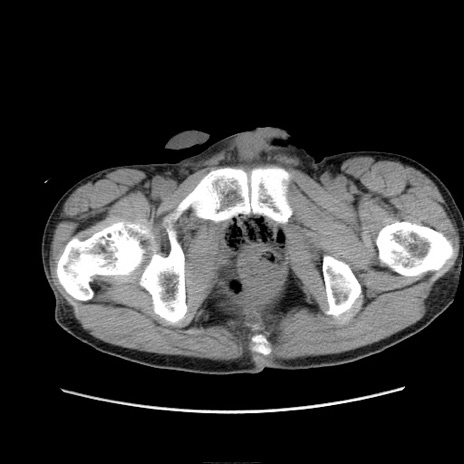

症例11(横断像)

【症例】 60歳代男性

【主訴】 下腹部痛

【現病歴】 本日夜中より下腹部痛の症状認め、受診。

【既往歴】 膀胱癌(膀胱全摘+尿管皮膚瘻術) 、胃癌術後

【身体所見】 BT 35.3℃、PR 58/min、BP 136/98mHg、腹部平坦、軟、腸蠕動音±、ストマ留置あり、左上腹部~正中部に圧痛あり、反跳痛なし。

【データ】WBC 5100、CRP0.01